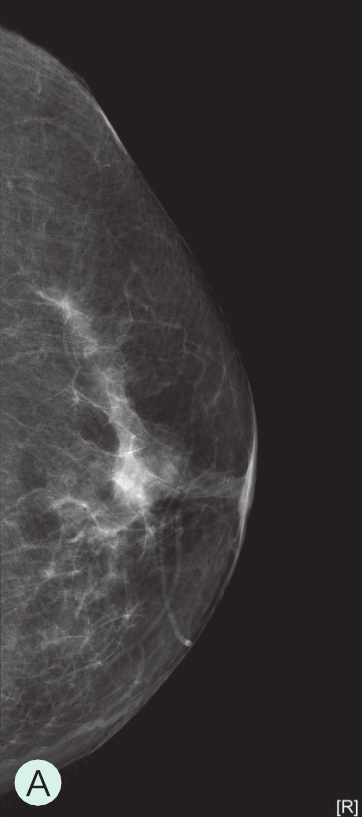

A级:几乎完全为脂肪型(图1-3-1A、图1-3-2A、图1-3-3A)。

图1-3-1 乳腺X线不同乳腺密度

A.脂肪型;B.散在致密型;C.不均匀致密型;D.极度致密型